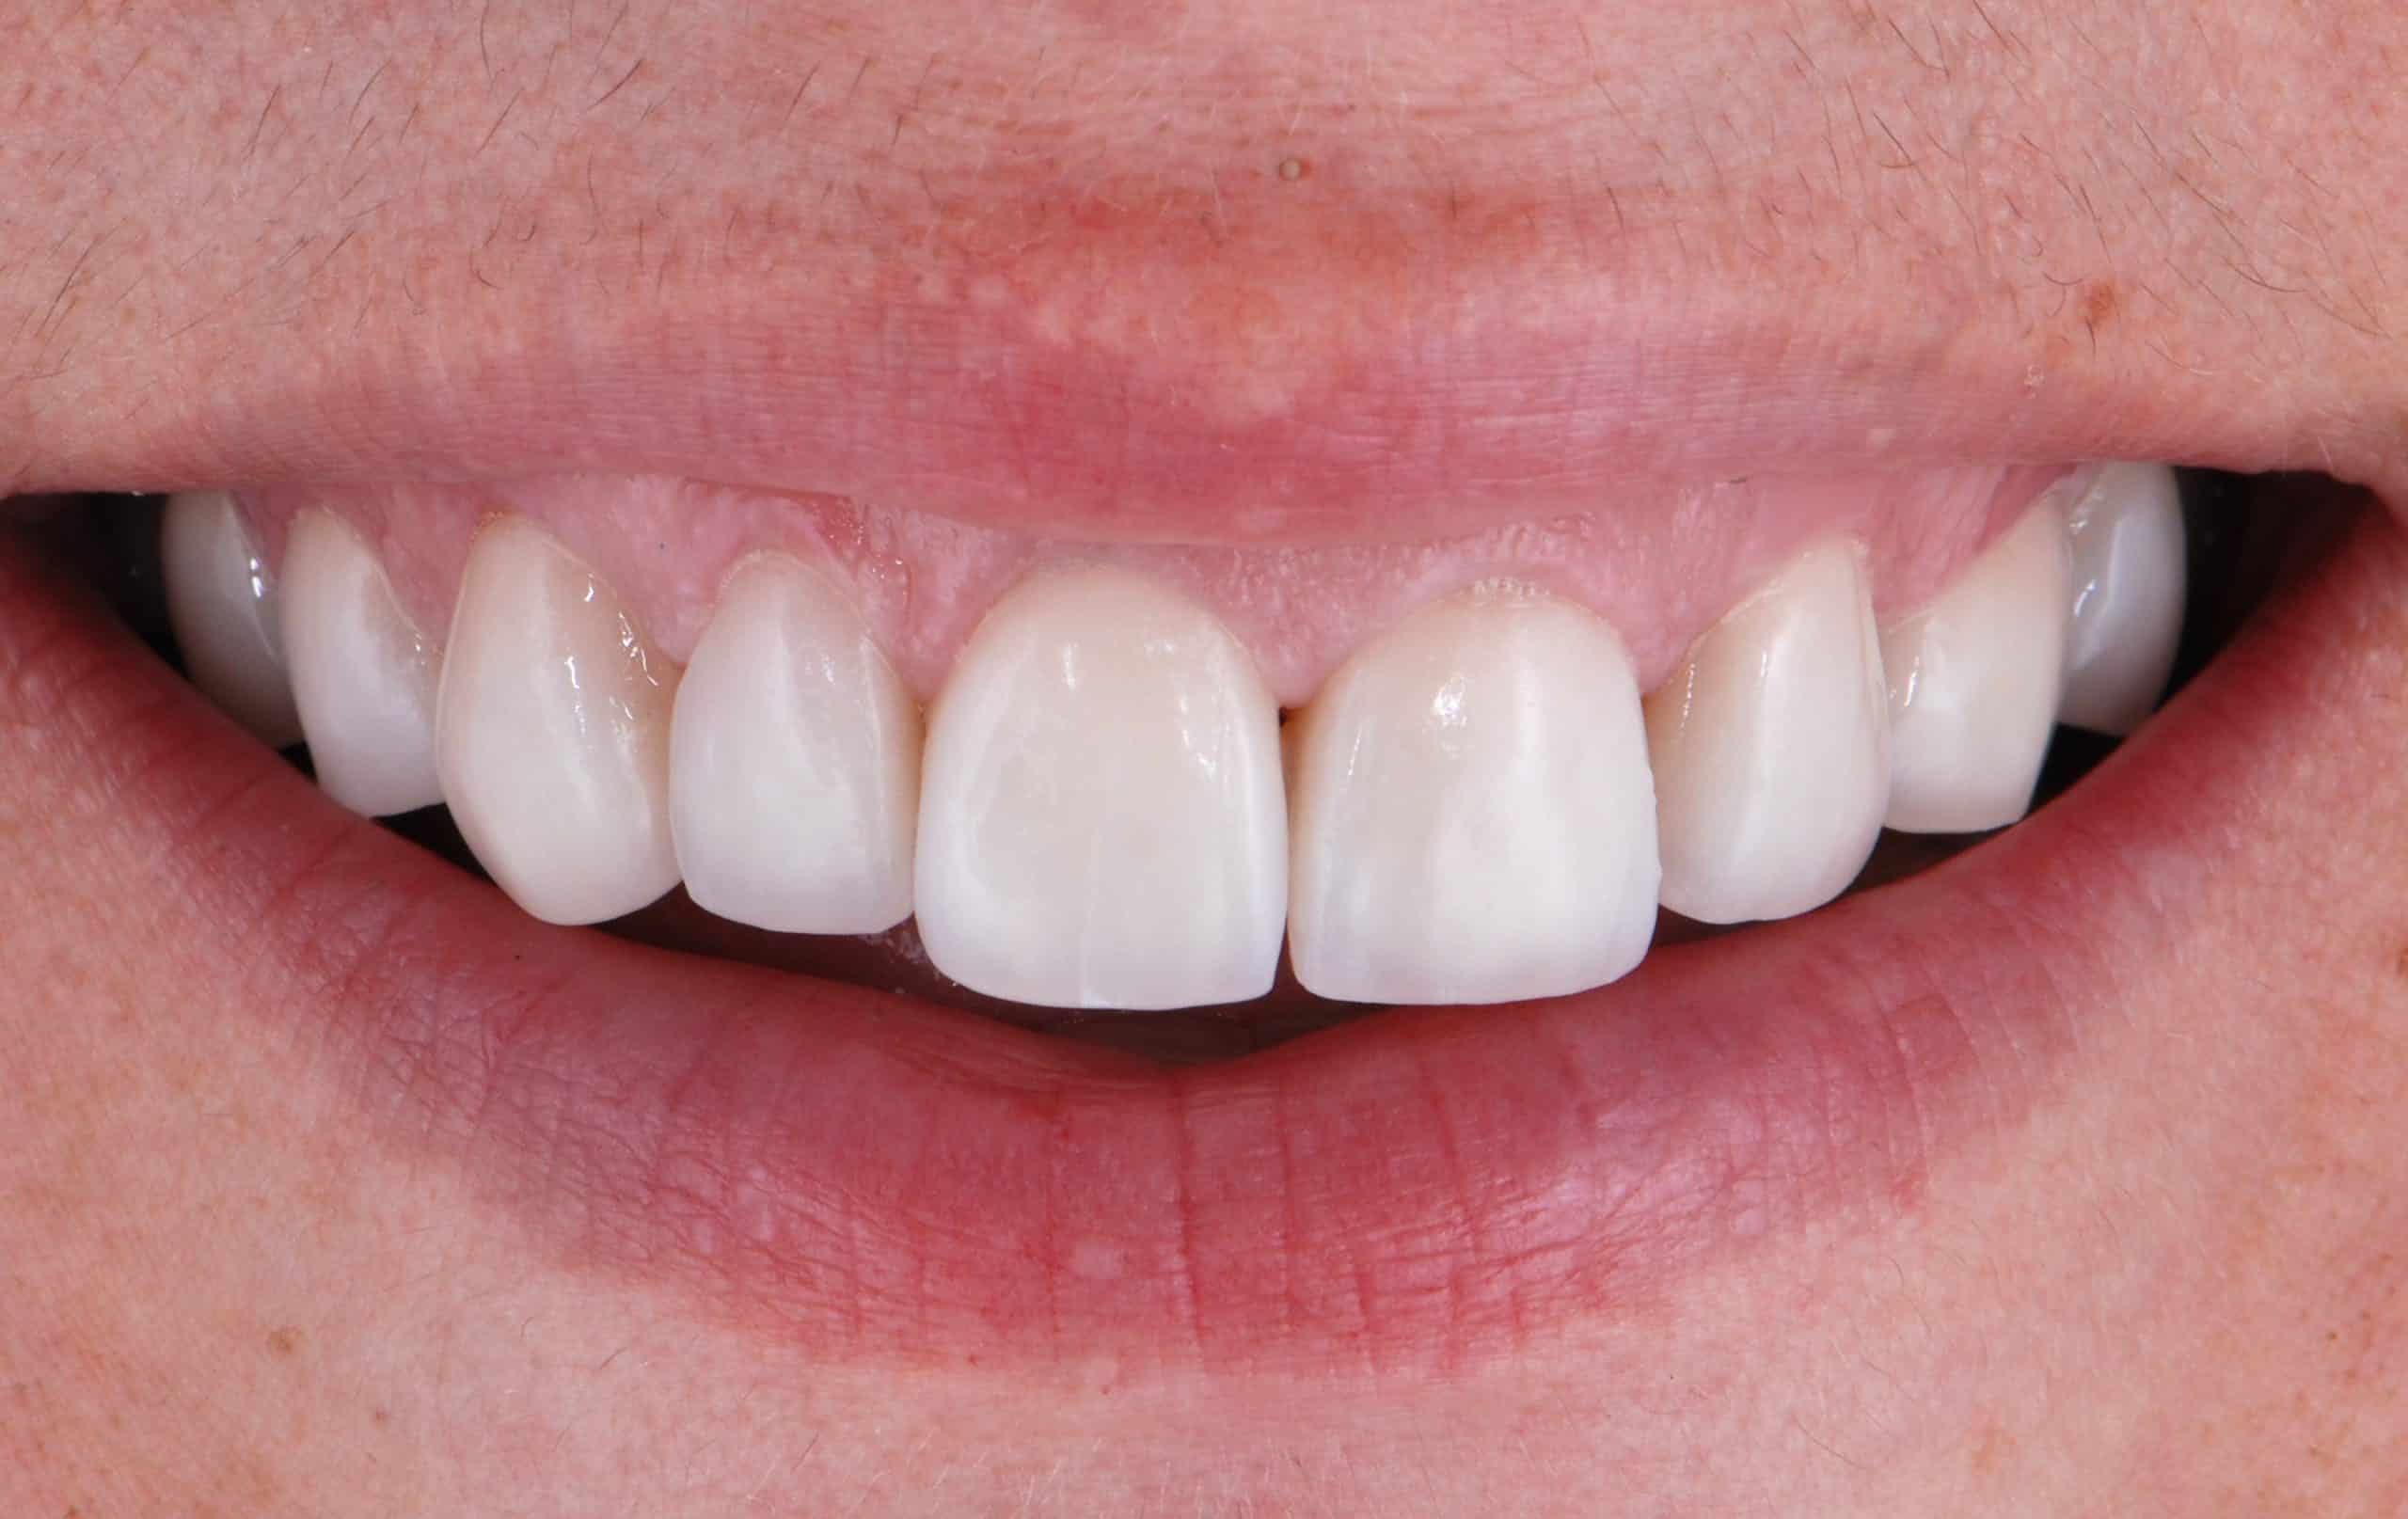

Caso 3

Paciente joven que quiere blanquear dientes sin hacer ningun tratamiento invasivo. Se realiza blanqueamiento zoom en una sesión.